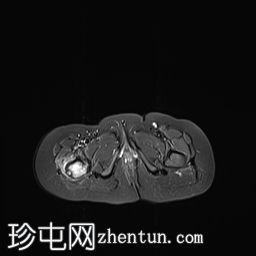

髋部

MRI

冠状位

T1

轴向

轴向PD

脂肪饱和度

轴向T1

C+脂肪饱和度

右上股骨大转子正下方外侧皮质区可见一小的皮质基部病变,边缘呈低信号,大小约为0.7 x 0.7厘米。

邻近的股骨近端骨干和股骨颈有水肿。

水肿有扩散至邻近肌肉的迹象。